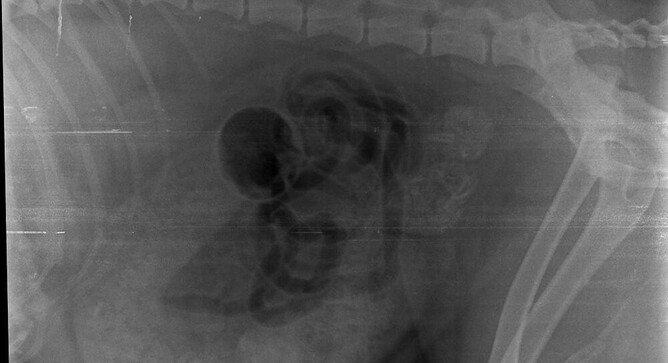

Spondylosis (boney fusion) of the back and tail base can narrow the pelvic outlet, as can an enlarged prostate gland in an entire male dog. Dogs with recurring episodes of constipation secondary to benign prostatic hypertrophy may benefit from being castrated.

Constipation can be a very serious medical condition and affected dogs should be treated promptly.